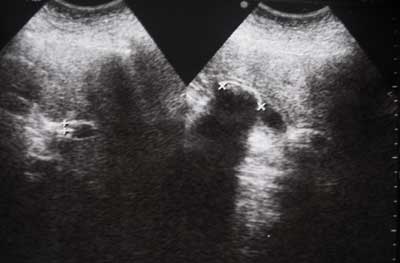

Ещё один пример похожей патологии ( здесь видно лучше

)

- IMG_6787w.jpg (11.12 КБ) 3095 просмотров

Ну, допустим, патология сходна только по первому слову ЖКБ.

В остальном - серьёзные различия.

Если это-холедохолитиаз, не видно расширения внутрипеченочных протоков. Необтурирующий? А желчный имеется в наличии?

В холедохе камешков нет! ЖП- в наличии (см. сонограмму)

острый калькулезный холецистит (размеры ЖП увеличены, стенка утолщена); во втором -

хронический. Или еще что-нибудь?